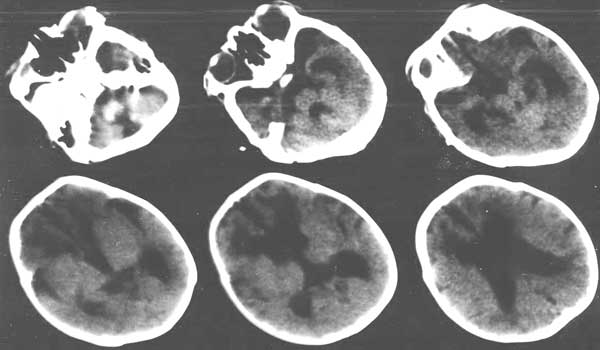

孩子一个月  体重减少700克 家里没钱治疗 只做了ct,医院建议放弃治疗

小孩以脑萎缩为主,请问是正常产吗

脑组织广泛密度减低,以白质为明显,其中又以双侧额叶白质呈囊性改变,且与扩大的侧脑室相贯通,考虑:1、严重缺血缺氧性脑病;2、脑先天发育异常。

请上传这提供生产史及病情,诊断才有科学行.凭感觉考虑:脑先天发育异常.

严重缺血缺氧性脑病脑室和脑沟不会有如此宽大吧.因为脑缺氧要造成脑水肿,脑室和脑沟应当变小.

向你的朋友表示慰问,节哀顺便吧,该患儿额叶皮质变薄,脑沟加深,应该是脑先天性发育异常。在现今社会,生存代价太大。